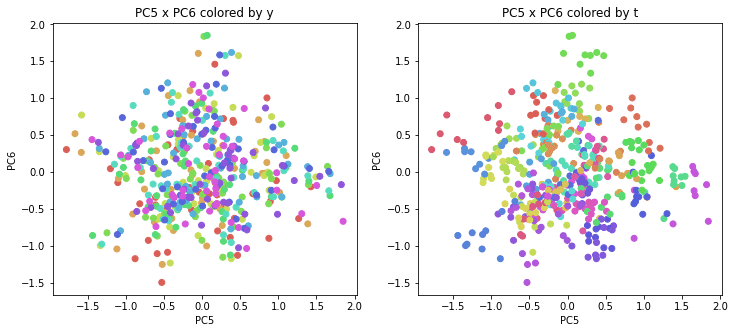

PCAの結果の第n主成分をPCnと表記します。

医療費データの場合と同様に、PCAの結果を見やすく表示するため、seabornのカラーパレットを使って、年月別、都道府県別に色分けして図示してみます(左側が年月別に色分け、右側が都道府県別に色分け)。PC1~PC8まで表示しました。

医療費データの場合ほどはっきりとはしていませんが、PC2が概ね時間の経過を表す成分で、残りの成分が時点によって変わらない地域の特徴を表す成分となっているようです。

また、PC1×PC3を見ると、47沖縄が他の都道府県からかなり離れたところに位置しており、沖縄の地域差が際立っているのが分かります。これは、以前別の記事で年齢階級のない健診データでPCAを実行した場合と似た結果となっています。